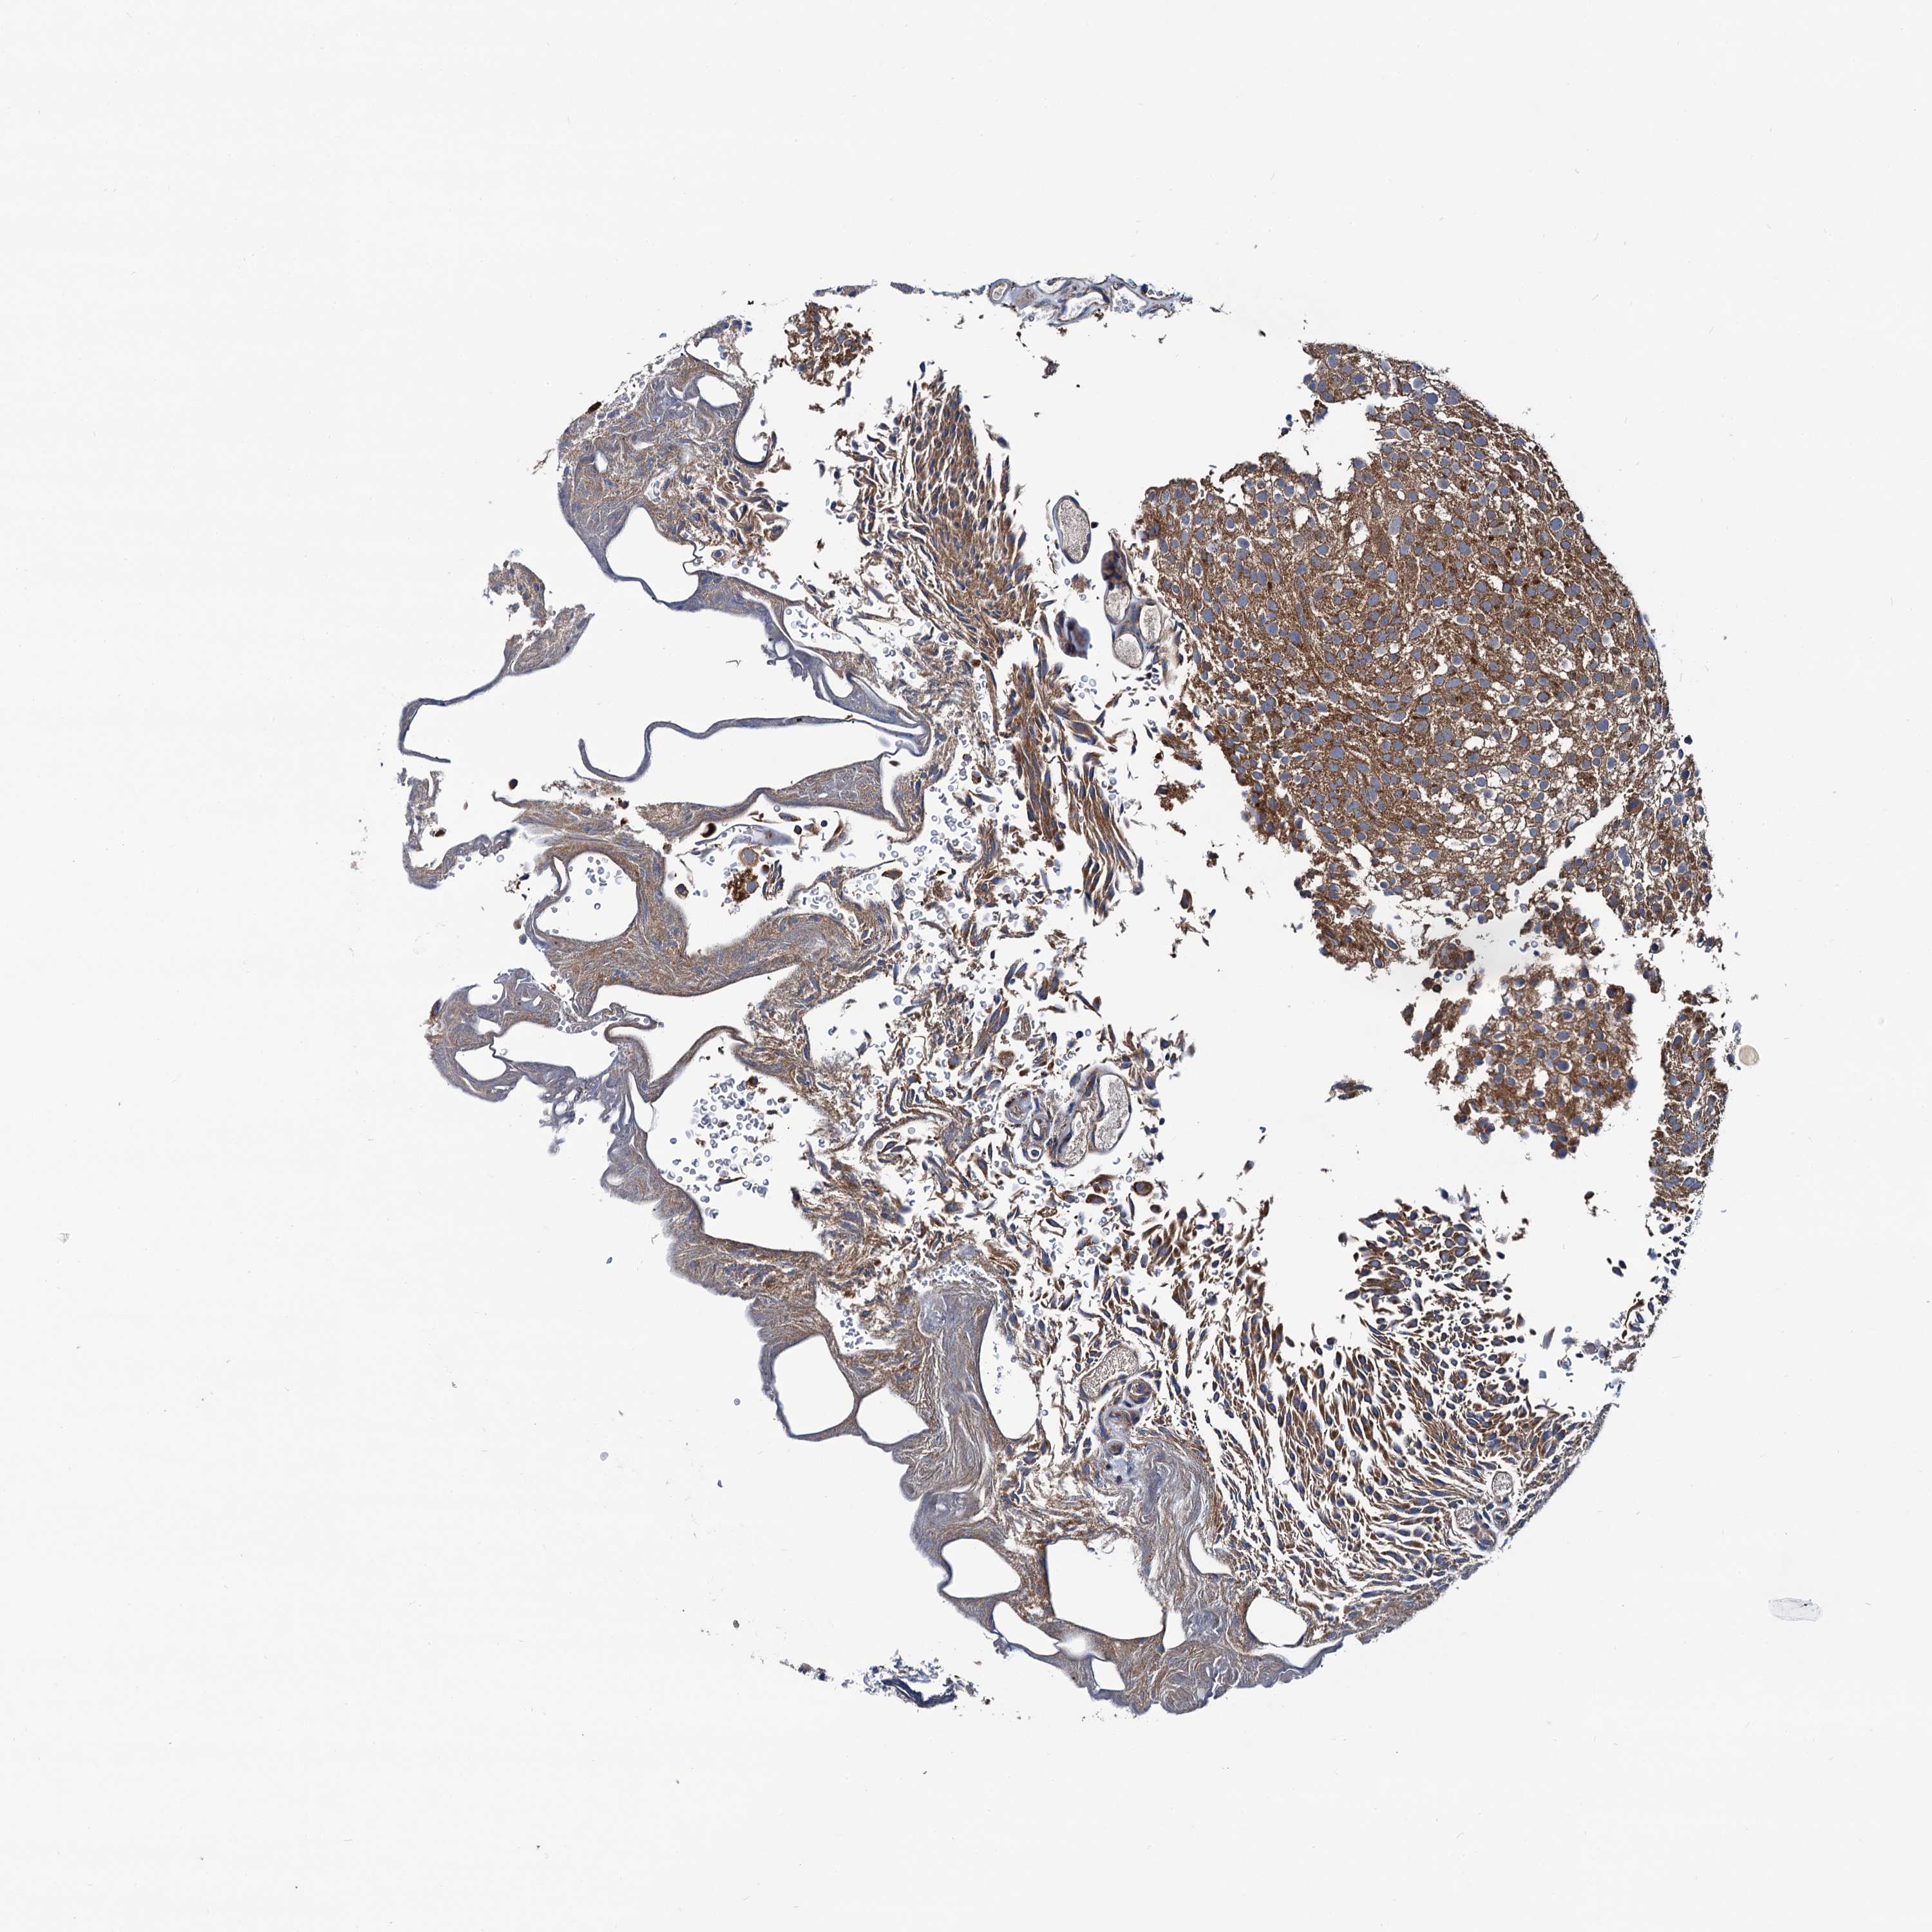

UROTHELIAL CANCER - Protein expressioni

A mouse-over function shows sample information and annotation data. Click on an image to view it in a full screen mode. Samples can be filtered based on level of antibody staining by selecting one or several of the following categories: high, medium, low and not detected. The assay and annotation is described here.

Note that samples used for immunohistochemistry by the Human Protein Atlas do not correspond to samples in the TCGA dataset.

Antibody stainingi

Antibody staining in the annotated cell types in the current human tissue is reported as not detected, low, medium, or high, based on conventional immunohistochemistry profiling in selected tissues. This score is based on the combination of the staining intensity and fraction of stained cells.

Each image is clickable and will lead to virtual microscopy that enables deeper exploration of all samples and also displays staining intensity scores, fraction scores and subcellular localization as well as patient and tissue information for each sample.

Antibody HPA020873

Antibody HPA040413

Staining

High

Medium

Low

Not detected

Intensity

Strong

Moderate

Weak

Negative

Quantity

>75%

75%-25%

<25%

None

Location

Nuclear

Cytoplasmic/membranous

Cytoplasmic/membranous,nuclear

Urothelial carcinoma, High grade

Urothelial carcinoma, Low grade

Urothelial carcinoma, NOS